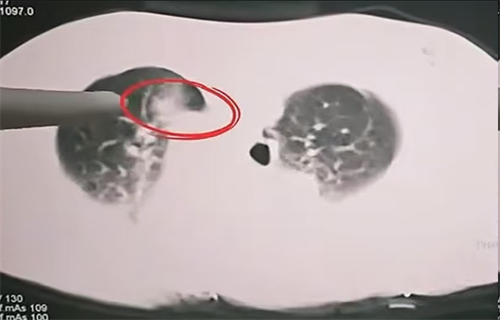

消融范围完美覆盖肺部病灶

微波消融技术是指在CT或超声引导下进行局部麻醉,将仅2毫米的消融针精准穿刺至肿瘤内部。针尖释放的微波能量可在60秒内将局部温度升至80-120℃,通过高温使癌细胞蛋白质变性坏死,但对周围健康组织的影响非常小,可以提高患者机体的免疫力,抑制肿瘤细胞的扩散。

该项技术对于高危位置肿瘤,可做到:1.精准控温,实时监测温度,避免灼伤血管、气管等关键结构。2.微创安全,仅需局部麻醉,创口如针孔,术后12~24小时即可下床。3.协同治疗:可与靶向药、免疫治疗联合,延缓耐药并清除残余病灶。